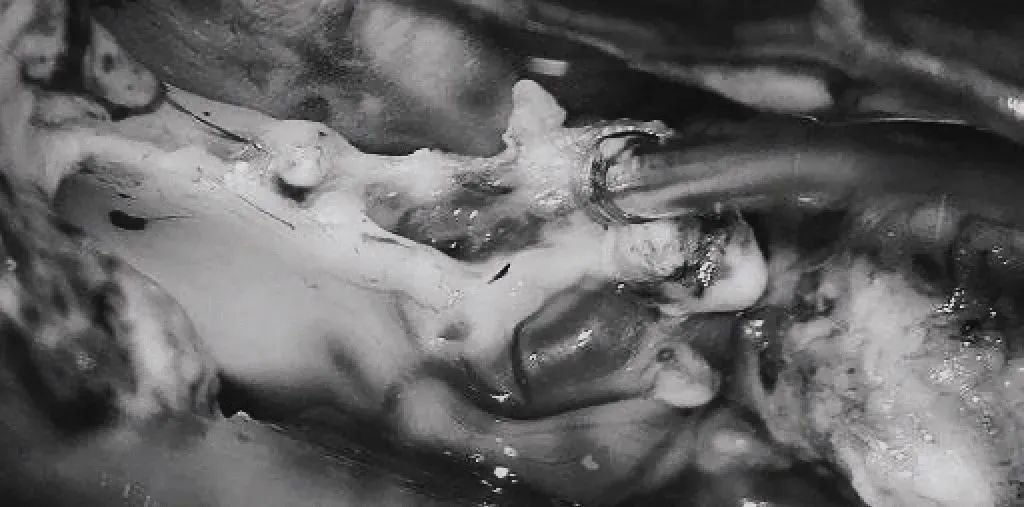

▼双额开颅,打开纵裂(鼻朝右,中线水平位,重力牵拉右侧半球),显露胼胝体、CmaA和PcaA。切开胼胝体2.5cm,显露透明隔内的AVM,大致显露ACA。

▼将AVM后缘向前牵离穹窿。

▼在透明隔底部保留FoM、穹窿和右侧SepV。

▼引流静脉变黑。

▼引流静脉进入ICV处电凝。完全切除AVM。